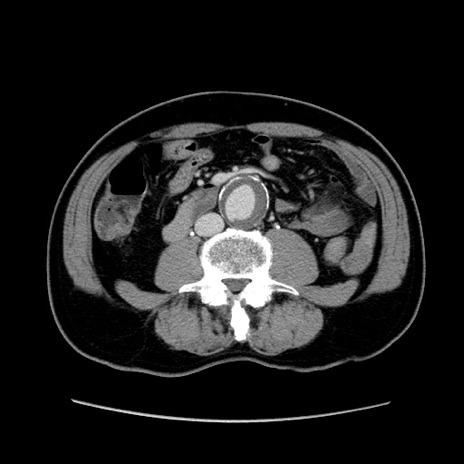

症例34(横断像)

【症例】60歳代 男性

【主訴】右鼠径部膨隆

【現病歴】1年程前より右鼠径部膨隆あり。自己にて還納可能だったため放置していた。3時間前より右鼠径部の脱出を認め、還納困難となり受診。

【既往歴】高血圧

【身体所見】右鼠径部に小児頭大の膨隆あり。弾性硬であり、用手還納は困難。左鼠径部にも膨隆を認める。脱出はなし。

【データ】WBC 15500、CRP 測定なし